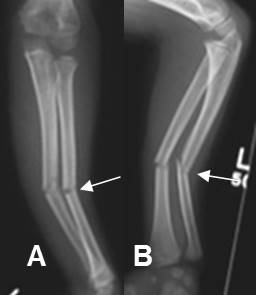

Fig 64. Fractura en leño verde.

A: Rx AP y B: Rx lateral. Fractura en leño verde del cúbito distal. (Flechas delgadas). Adicionalmente hay fractura en torus del radio distal. (Flecha gruesa).

Fig 65. Fractura en leño verde.

A: Rx AP y B: Rx lateral. Fracturas en leño verde del radio y cúbito con rotación y angulación anterior y en valgo.